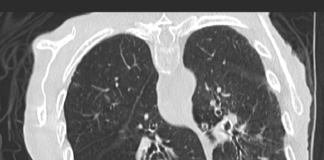

Paziente di sesso femminile, 48 anni. Anamnesi patologica remota muta. La paziente è residente a...